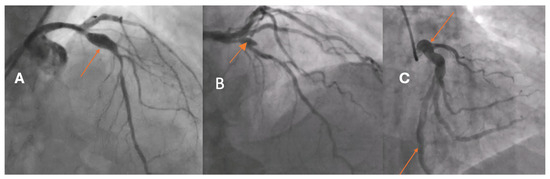

Optical and Scanning Electron Microscopy Thrombus Findings in Patients with STEMI Undergoing Primary Versus Rescue PCI

by Stella Marinelli Pedrini, Thiago P. A. Aloia, André H. Aguillera, Paula M. P. S. Gomes, Jamil R. Cade, Francisco Sandro Menezes-Rodrigues, Bárbara P. Freitas, Marco T. Souza, Francisco A. H. Fonseca, Marcos Danillo Oliveira, Breno O. Almeida, Andrey J. Serra, Renato D. Lopes, Rita Sinigaglia-Coimbra and Adriano Caixeta

Biomedicines 2025, 13(9), 2235; https://doi.org/10.3390/biomedicines13092235 - 11 Sep 2025

Background: The mechanisms underlying fibrinolysis failure in patients with STEMI who are undergoing a pharmacoinvasive strategy appear to be multifactorial and may be associated with the thrombus’s architecture and composition. Objective: We aimed to compare the thrombus composition in patients with [...] Read more.

Background: The mechanisms underlying fibrinolysis failure in patients with STEMI who are undergoing a pharmacoinvasive strategy appear to be multifactorial and may be associated with the thrombus’s architecture and composition. Objective: We aimed to compare the thrombus composition in patients with STEMI who were undergoing rescue percutaneous coronary intervention (rPCI) versus primary PCI (pPCI) using optical microscopy (OM) and scanning electron microscopy (SEM). Methods: Fifty-three patients were prospectively enrolled, with twenty-five undergoing rPCI and twenty-eight undergoing pPCI. After thrombus aspiration, each harvested fragment was divided into two pieces: one was analyzed using OM with a 60× magnifying lens on hematoxylin–eosin-stained samples, and the other with SEM at 5000× magnification. Results: Patients who underwent rPCI had significantly higher C-reactive protein levels and a longer ischemic interval at admission compared to those treated with pPCI (9.92 h [range: 1.58–106.17] vs. 2.14 h [range: 0–48]; p < 0.001). Optical microscopy analysis revealed that thrombi from rPCI patients exhibited a significantly higher erythrocyte area percentage (18.36% [range: 0.3–50.08] vs. 0.91% [range: 0–70.1]; p = 0.001), a lower fibrin content as assessed by optical microscopy (79.49% [range: 49.2–98.25] vs. 94.43% [range: 29.19–99.92]; p = 0.006), and a greater amount of cholesterol crystals as measured by SEM (1.73 μm2 [range: 0–18.51] vs. 0.08 μm2 [range: 0–0.71]; p < 0.001). Conclusions: The thrombus composition of patients with STEMI who are undergoing rPCI had higher amounts of erythrocytes and cholesterol crystals and a lesser area occupied by fibrin compared to those undergoing pPCI. The composition of thrombi in rPCI could potentially contribute to the failure of fibrinolytic therapy within a pharmacoinvasive strategy. Full article

Show Figures